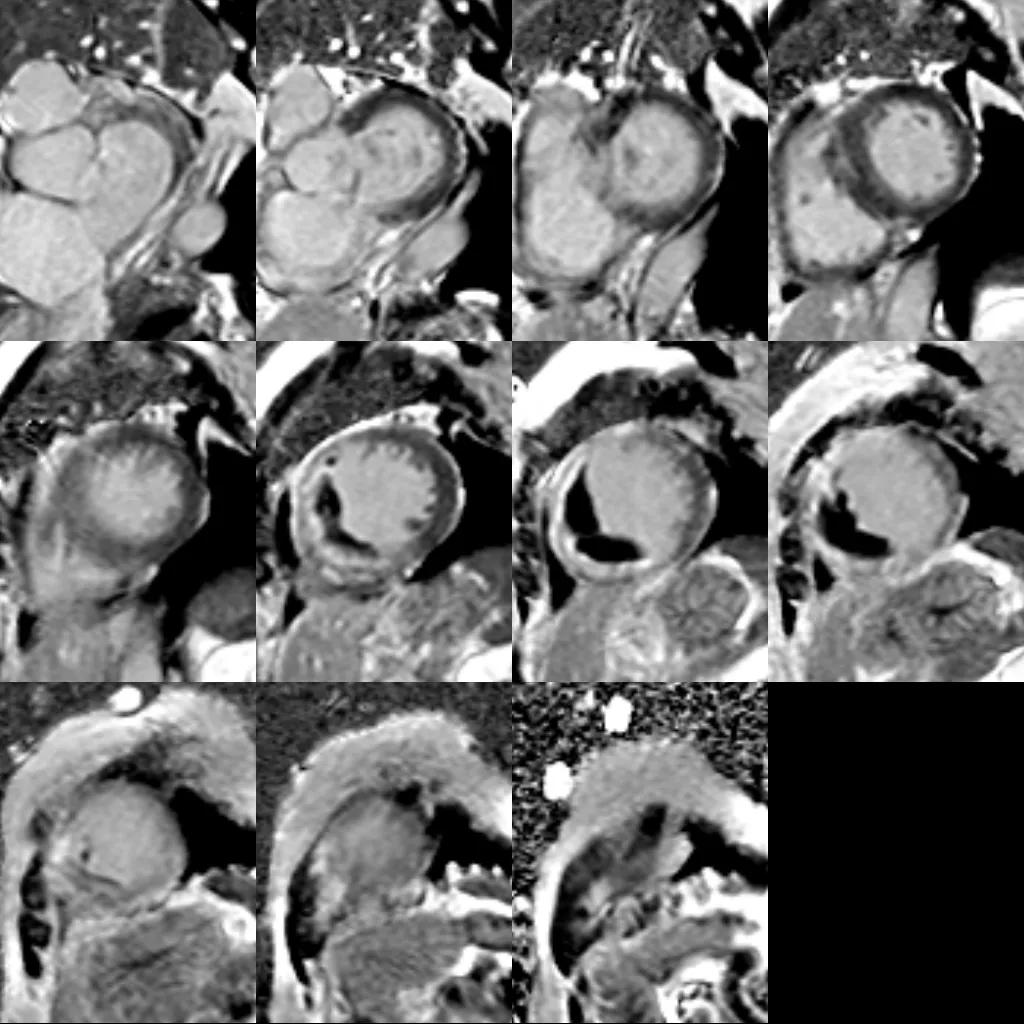

(3)核磁表现同时具备心肌梗死(室间隔基底段至心尖部心内膜下延迟强化)与应激性心肌病(“章鱼篓”样改变,且延迟强化未累及室壁瘤节段)的特征,考虑患者存在心肌梗死合并应激性心肌病。

基于以上3点及患者病史、临床症状等,推测发病过程可能为:急性心肌梗死诱发应激性心肌病,从而出现后续SAM征、流出道梗阻、ST段再次抬高等变化及心脏核磁提示“章鱼篓”样形态演变,均可视为在急性心肌梗死的基础上,应激进一步加重病情出现一系列并非心肌梗死的变化。由于需证明室壁异常运动的可逆性,目前还无法明确就诊,需进一步随访3个月。

患者入院时的临床表现与急性冠状动脉综合征(ACS)和/或急性心力衰竭(HF)极为相似(胸痛、呼吸困难、肺水肿、心源性休克甚至心脏停搏),但也可能表现为乏力、咳嗽等不典型轻症。心电图改变包括ST段抬高/下降、T波倒置、窦速等,没有单一ECG标准。超声心动图急性期多表现为左心室心尖部室壁运动异常,心尖部呈球形膨出,基底段代偿性运动增强,也可见基底段或中间段收缩障碍,范围常超出单支冠状动脉供血分布区域,左心室射血分数明显降低。生物学标志物方面,约90%的患者肌钙蛋白水平升高,但通常只是轻度升高,心肌肌钙蛋白峰值与ACS相比明显降低,左心室室壁损伤程度与心肌坏死生物标志物的升高程度不呈正比,可能与可逆性心肌损伤有关。冠脉造影通常在检查时未发现有阻塞性冠状动脉解剖结构。